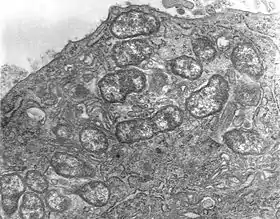

Збудник хвороби — Orientia tsutsugamushi (також раніше Rickettsia orientalis), є облігатною (обов'язковою) внутрішньоклітинною грамнегативною бактерією. O. tsutsugamushi дуже схожа на інші рикетсії і відповідає всім класифікаціям родини Rickettsiaceae. Це було продемонстровано високим ступенем гомології (90-99 %) по рибосомальній послідовності 16S. Однак клітинна стінка відрізняється від інших рикетсій, оскільки у O. tsutsugamushi відсутні пептидоглікани та ліпополісахарид. Цей патоген не має вакуолярної мембрани, таким чином, він вільно розмножується в цитоплазмі інфікованих клітин, на відміну від інших рикетсій, які зростають у ядрі. При мікроскопії вони виглядають як диплококи або диплобацили завдовжки 0,3-1,5 мкм і завширшки 0,2-0,5 мкм. При фарбуванні за Романовським-Гімзою вони фарбуються у темно-пурпуровий відтінок, проте вони є єдиним видом рикетсій, який не фарбується по Здродовському і Макіавелло.